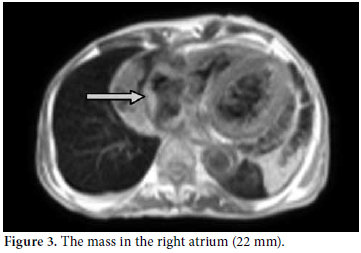

A 61-year-old male patient was admitted to our outpatient unit with dyspnea, edema on the legs, and chest pain. The physical examination was unremarkable except for exophthalmos, tachypnea, S3 edema, and bilateral pretibial pitting edema, and the laboratory investigation revealed the following levels: blood urea nitrogen 94 mg/dL, creatinin 1.38 mg/dL, and C-reactive protein (CRP) 1.53 mg/dl. The anti nuclear antibody (ANA) revealed a negative result. The globulin levels were within normal limits; therefore, IgG and E levels were not analyzed. The patient had no history of autoimmune or allergic diseases. An echocardiographic evaluation was performed to rule out heart failure and massive pericardial effusion, and a mass at the right atrial wall was detected. Nearly 1500 cc pericardial fluid was aspirated by pericardiosynthesis for the relief of the dyspnea. The examinations for tuberculosis revealed negative results, but atypical mesothelial and inflammatory cells were seen in the cytological evaluation. Therefore, computed tomography (CT) of the abdomen and thorax was ordered for further evaluation and pericardial effusion and periaortitis was detected beginning from the arcus and lasting to the abdominal aorta (Figures 1 and 2). On the cardiac CT scan, three soft tissues arising from the right coronary artery and extending to the right atrium were seen (Figure 3). The serologic tests for perinuclear anti-neutrophil cytoplasmic antibodies (p-ANCA) and cytoplasmic anti-neutrophil cytoplasmic autoantibody (c-ANCA) were negative. The radiological evaluation of the exophthalmos with cranial CT revealed bilateral retro-orbital pseudotumors, although the thyroidstimulating hormone level was normal (Figure 4). By all of these radiological findings, IgG4-related sclerosing vasculitis was first suspected, and the level of IgG4 was found to be 148 (0-125) U/ml. The patient was referred to the cardiovascular surgeons for a biopsy from the mass in the right atrium. The histological evaluation of the biopsy material revealed lymphoplasmacytic infiltration fibrosis, a lymphoid follicle, and eosinophilic infiltration. These findings were concordant with IgG4-related sclerosing vasculitis. The arterial constrictions in the right coronary artery and circumflex artery were removed by percutaneous balloon angioplasty and two cardiac stents a cardiac pacemaker were implanted.

The appropriate treatment was ordered as a pulse steroid of 1000 mg prednisolone and 500 mg cyclophosphamide every month in conjunction with oral immunosuppressive therapy. A radiological evaluation after three months revealed significant response and regression of the lesions. The mass in the right atrium had decreased to 16 mm, and the lesion on the retro-orbital area had decreased to 11 mm on the right and 12 mm on the left.